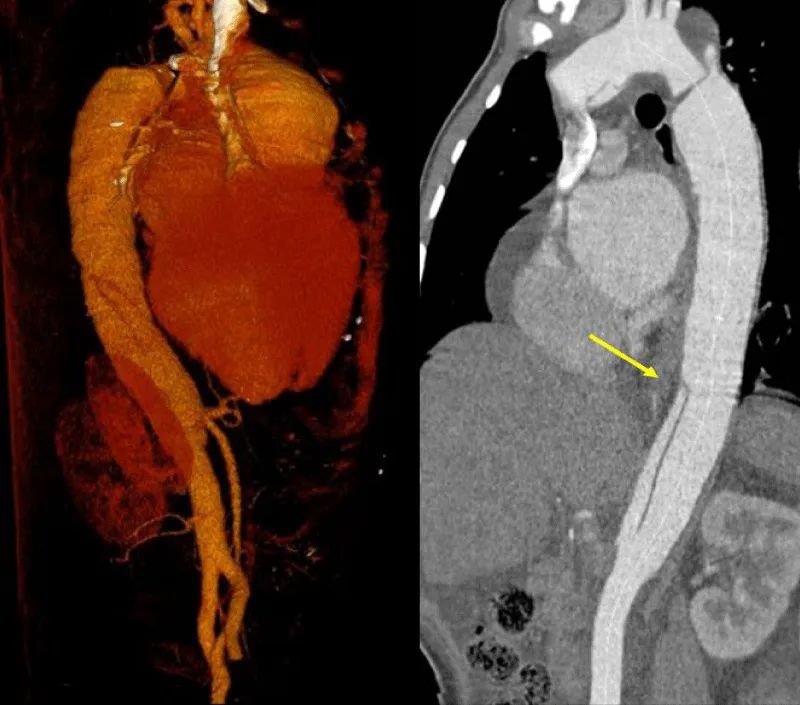

Transthoracic echocardiography (Figures 3,4) found a dilated aortic root (52 mm) with an ultrasound image of the intimal flap, and significant bi-ventricular dilation (left ventricular end-diastolic diameter of 72 mm). Systolic functions of both ventricles were severely impaired (LVEF of 24% and TAPSE of 10 mm). There was severe aortic regurgitation with a regurgitant orifice area of 35 mm². Dissection of an aortic aneurysm on dilated cardiomyopathy was diagnosed and confirmed by aortic CT scan (Figure 5); it was a type A aortic dissection with very severe dilation of the aortic root at the origin of the first branch of the supra-aortic trunks. A Type B dissection coexisted along, with an aortic dilation beginning far from the origin of the last branch of the supra-aortic trunks up to the iliac bifurcation. The Marfan disease was diagnosed despite the absence of genetic testing and a family history of the syndrome. An ophthalmological assessment could not be carried out. Medical treatment with diuretics, vasopressin amines, and analgesics was started and enabled slight improvement. The patient was later referred for surgical management through the financial support of a philanthropic sponsor. He was operated on March 7th, 2013 under cardiopulmonary bypass, using the Tirone David procedure. During surgery, the impression of two separate aortic dissections was confirmed: the former one of type B which previously went unnoticed, and the recent one of type A which determined the patient current clinical condition. After surgery, congestive heart failure was persistent, but during follow-up in the outpatient unit, the clinical condition remained stable under diuretic, ACE inhibitor, and oral anticoagulation. Unfortunately, the patient died four years later in 2017, due to poor medical follow-up.

Figure 5: Aortic CT angiography: note the two levels of the intimal tear. The first is located in the ascending aorta with aneurysmal dilatation of this aortic portion and the second dissection originating distally on the abdominal aorta up to the iliac bifurcation.